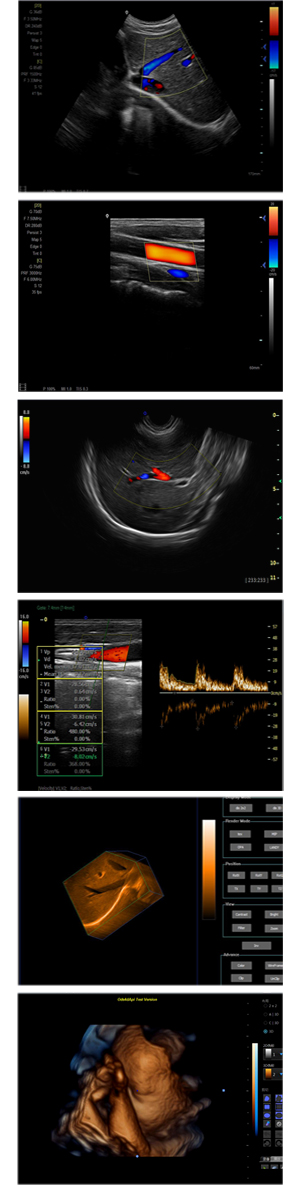

XF-7600型,秉承先鋒彩超技術之精華,擁有高雅大氣的獨特外型,為最新一代應用型數字彩色多普勒診斷系統,魅力與實力相融合。可廣泛適用于腹部、婦產科、心臟、小器官、乳腺、肌骨及外周血管等諸多方面的診查,讓您在臨床超聲診斷應用領域得心應手,綻放異彩!

● 3D/ 4D成像技術/選配

● 應用于腹部、腎臟、泌尿系統、產科、婦科、盆腔、大動脈、肌肉組織、小器官、乳腺、心臟等

● 能量多普勒成像(PDI)

● 彩色血流量圖(CDE)

● 脈沖頻譜多普勒成像(PW)